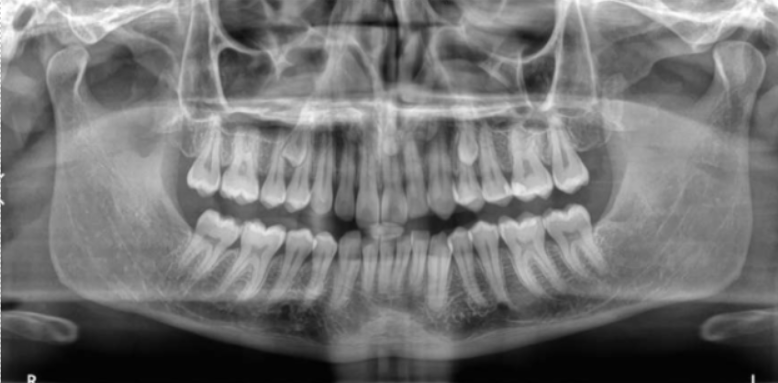

Treatment depends on age, position, and severity. The most common approach involves surgical exposure of the tooth, often followed by orthodontic guidance to help it erupt into its proper position.

We use 3D imaging to locate the tooth precisely and work closely with your orthodontist to coordinate care. The procedure is usually done under sedation to ensure a smooth experience.

We use advanced 3D imaging technology to locate the tooth precisely and carefully plan the procedure. This ensures minimal disruption to surrounding teeth and bone, allowing for safer and more predictable outcomes. Our oral surgeons work closely with your orthodontist to coordinate care and monitor progress throughout the treatment. Procedures are typically performed under sedation or local anesthesia to provide a comfortable and stress-free experience.